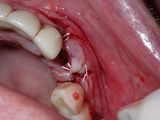

Olympus TG-6

1/100s f/14.0 at 18.0mm iso200 full exif